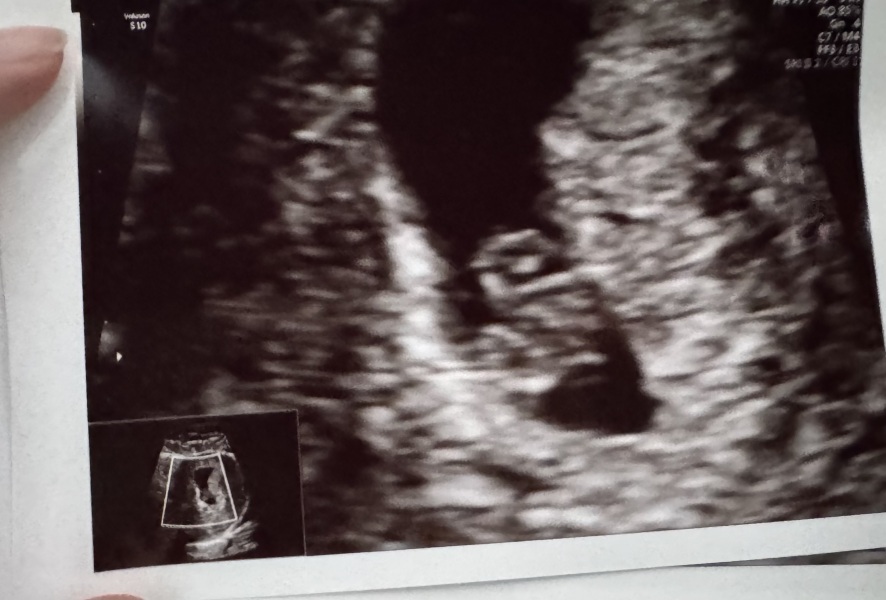

Sorry for the radio silence! Scan on Sunday went well, all looking good and on track ❤

Since we’ve had that scan we made the decision to tell the kids and our parents/siblings - they were all thrilled and just been in a little bubble really. Although I’ve been feeling so lousy and sick, I literally was sick watching the I’m a Celeb eating trial as I just couldn’t stomach it 😅

Photo of our little jellybean 😍